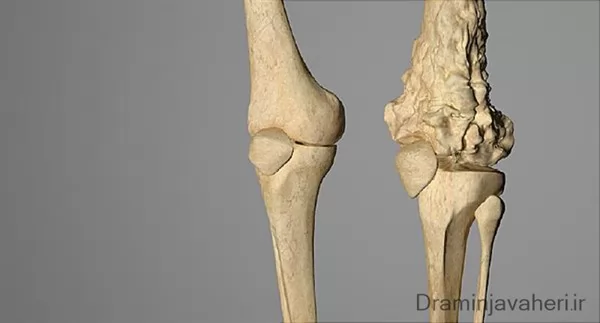

عکس سرطان استخوان

عکس سرطان استخوان. برخی از انواع اصلی سرطان استخوان عبارتند از. سرطان مغز استخوان یکی از انواع سرطان است که به دلیل اختلال در تولید گلبول ها و پلاکت های بدن به وجود می آید. رشد ناهنجار استخوان می تواند بدخیم یا خوش خیم باشد. این تصویر سرطان استخوان است که کاملا روی جمجمه قابل دیدن می باشد.

روش های عکس برداری می توانند به تعیین محل و اندازه ی تومورهای استخوان و گسترش یا عدم گسترش آن ها به سایر نقاط بدن کمک کنند. در این مقاله با علائم سرطان مغز استخوان و نیز روش های درمان آن آشنا می شوید. یک تومور رشد غیر طبیعی بافت در بدن است. سلول های توموری توانایی تنظیم کردن ندارند بنابراین سلول های بیشتری تولید می کنند و منجر به تشکیل یک توده می شوند در حالی که بسیاری از تومورها سرطانی.